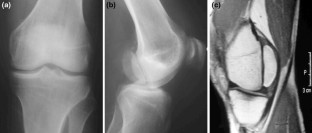

Nonunion of a Hoffa fracture in an adult

The coronal fractures of femoral condyles, known as Hoffa fractures, are a rarity. Conservative management often leads to unsatisfactory results and nonunion. In this study, we present a case of a 35-year-old patient with an established nonunion of medial Hoffa fracture of right knee treated with open reduction and internal fixation.

Fig. 2